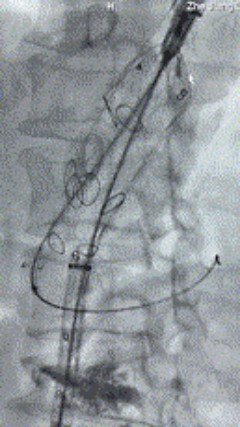

5. 撤出腹腔干导丝导管,经左肱动脉长鞘继续抓捕预置导丝将长鞘超选至另一侧内分支,后超选进肠系膜上动脉,沿导丝送入先健覆膜支架10*100mm一枚,近端重叠内分支,远端重叠于肠系膜上动脉,并予以10mm球囊后扩,手推造影显影良好。

6. 解除束径,打开近端后释放,经肱动脉长鞘超选支架外分支,并进一步超选右侧肾动脉,交换加硬导丝,送入覆膜支架6*50mm和7*60mm各一枚,并予以球囊后扩张,手推造影显影良好。

7. 经长鞘重新选入左侧外分支,并超选进左肾动脉,沿导丝送入外周血管覆膜支架7*60mm一枚,并予以球囊后扩张,手推造影显影良好。